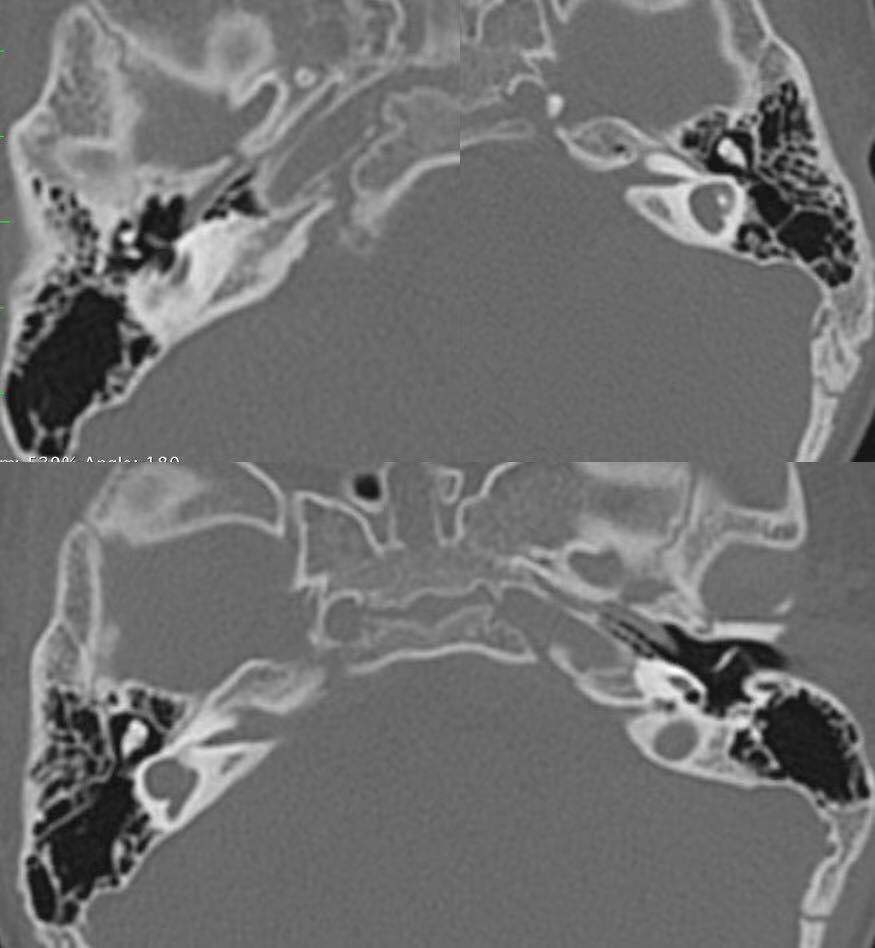

记者了解到,26月龄的聪聪于今年初到上海九院耳鼻咽喉科就诊,虽然体重身高发育正常,但自幼听力差,曾被诊断为“双侧极重度感音神经性聋”,也正因如此,言语功能也没有发育完善。聪聪的家长为了能让孩子重建听力,曾带着他辗转就诊于全国多地医院,但由于聪聪存在双侧耳蜗及双侧听神经未发育,属于人工耳蜗植入的禁忌症,因此一度认为听力重建希望渺茫。直到在九院听力中心就诊后,医务人员对聪聪进行了全面细致的检查评估,认为他适合进行“人工听觉脑干植入”(auditory brainstem implant, ABI)。

什么是ABI?与普通人工耳蜗有什么区别呢?吴皓介绍,人的听觉系统从外周起一级级向中枢传递,其中重要的是耳蜗传向耳蜗核,耳蜗是内耳的一部分,属于外周听觉器官,耳蜗核是初级听觉中枢神经核团,中间由听神经相连。“大多数感音神经性耳聋都是由于耳蜗出现了问题,那么这个时候植入人工耳蜗就可以解决问题,人工耳蜗就相当于代替了耳蜗功能。”

不过,仍有一部分患者由于病变部位更靠近中枢,无法借助人工耳蜗重获听力。为此,一种更为先进的治疗方案——听觉脑干植入悄然展开,使得这些患者也有望重建听力。“ABI是将听觉植入装置直接植入脑干的耳蜗核,外界声音将绕过人的耳蜗和听神经传导,直接到达脑干,刺激后耳蜗核不同的感受神经元所产生听觉神经冲动,并进行信号处理及编码,经中枢到达大脑皮层,产生有意义的听觉。”